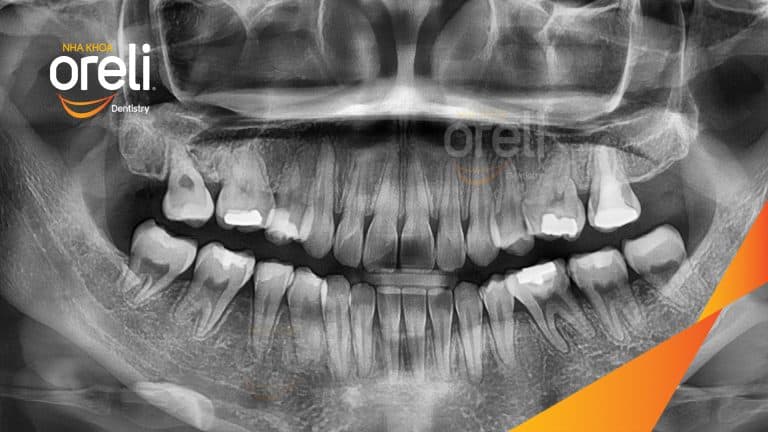

Ca niềng răng đặc biệt: kéo răng 7, 8 thay thế 3 răng 6 bị hư tại Oreli Niềng răngDi gần răng 7 8 Xem thêm